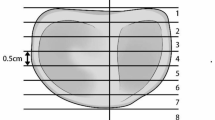

The shape and width of the flexion gap were assessed, based on four reference lines (2, 3, 4, and 5) and two points ‘P’ and ‘Q’ (Fig. 3). A pixel to millimeter-scale was set from the millimeter scale given in the slide before marking various lines.

Line 1 was defined as the longitudinal axis of the tibia, which was determined by connecting the midpoint of the width of tibial diaphysis at two levels. For sake of uniformity, the two levels for measuring the width were taken approximately 50 mm and 75 mm from the tibial intercondylar eminence. In slides with insufficient length of the tibia for marking these points, a minimum gap of 25 mm was maintained between the two points.

Line 2 was defined as the tibial osteotomy axis which was perpendicular to the longitudinal axis of tibia (Line 1). While marking the perpendicular line it was not always possible to get it exactly at 90°. In such cases, the marking was drawn to the nearest possible angle with a difference of less than 1°. However, while assessing the data, the tibial osteotomy axis was considered as perpendicular to the tibial longitudinal axis.

Line 3 was defined as the epicondylar axis connecting the lateral epicondylar prominence either to the medial sulcus (surgical epicondylar axis, SEA) or to the medial prominence (clinical epicondylar axis, CEA).

Line 4 was defined as the tibial articular axis which connected the proximal margins of the lateral and medial articular surfaces of the tibia.

Line 5 was made by connecting the posterior margins of the lateral and the medial femoral condyles.

The width of the medial and lateral joint gap was measured after marking points ‘P’ and ‘Q’ on medial and lateral femoral condyles respectively (marked at maximum convexity) and calculating the distance of point ‘P’ and ‘Q’ from line 4 i.e. tibial articular axis. The shape of the flexion gap in neutral and under varus and valgus stress was assessed by analyzing the angle between line 2 and line 3. This corresponds to the configuration of the flexion gap during the bone resection in the proximal tibia and posterior femoral condyles during the TKA. The angle between line 4 and line 5 was also determined as this represented the physiological separation of the tibiofemoral articular surfaces. The flexion angle was measured through sagittal images during the localizer series.